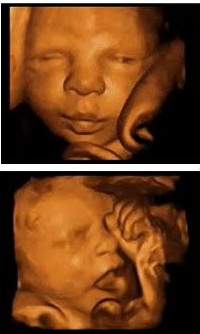

四维彩超,全称为四维彩色超声诊断仪,是上先进的彩色超声设备。四维彩超对准妈妈来说,其实是颗“定心丸”,因为它能够多方位、多角度地观察宫内胎儿的生长发育情况,为早期诊断胎儿先天性体表畸形和先天性心脏疾病提供准确的科学依据。而且对孕妇、胎儿等人群造成任何损伤和导致胎儿发育不良和伤残。更重要的是四维彩超还十分的经济实惠。

1、四维彩超系统超越了二维、三维超声的限制,不仅能够检查胎儿的生理指标,还使堆枯燥难懂的B超数据结果,变成清晰的动态图像可对胎儿的体格、健康发育状况进行检查,为早期诊断各种胎儿先天性体表畸形和先天性心脏疾病等提供准确全面的科学依据,让待产准妈妈们安心,家人放心!

2、显示结果直观,易于理解,便于准父母们对图像的认识和理解,也便于对胎儿病变和畸形的认识和理解,便于医生与准父母们的沟通。

4、能亲眼目睹胎儿在准妈妈肚子里的各种生理活动,增进准父母与胎儿的情感交流。

城阳玛丽妇儿医院温馨提示:般情况下,妊娠25-28周是做四维彩超的佳时间,这段时期检查,因为胎儿较小,羊水较多,胎儿活动度大,体表也比较丰满,有利于胎儿四维超声成像和胎儿畸形检查,是排畸的好时期。